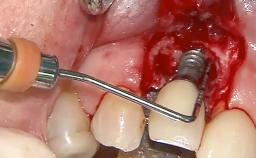

Surgical Management of Peri-Implantitis: Reconstructive Surgical Treatment with Three-Year Follow-up After Treatment

Despite anti-infective surgical treatment, some patients may experience recurrent infection and progressive bone loss requiring additional treatment. Removal of Implant Due to Recurrent Infection describes a conservative approach using an implant retrieval tool without the need for excessive bone removal or use of a trephine.

A 70-year-old female patient was referred by her general dentist to the periodontist for assessment and management of an infection associated with implant 36. The general dentist had noted suppuration on probing during examination.